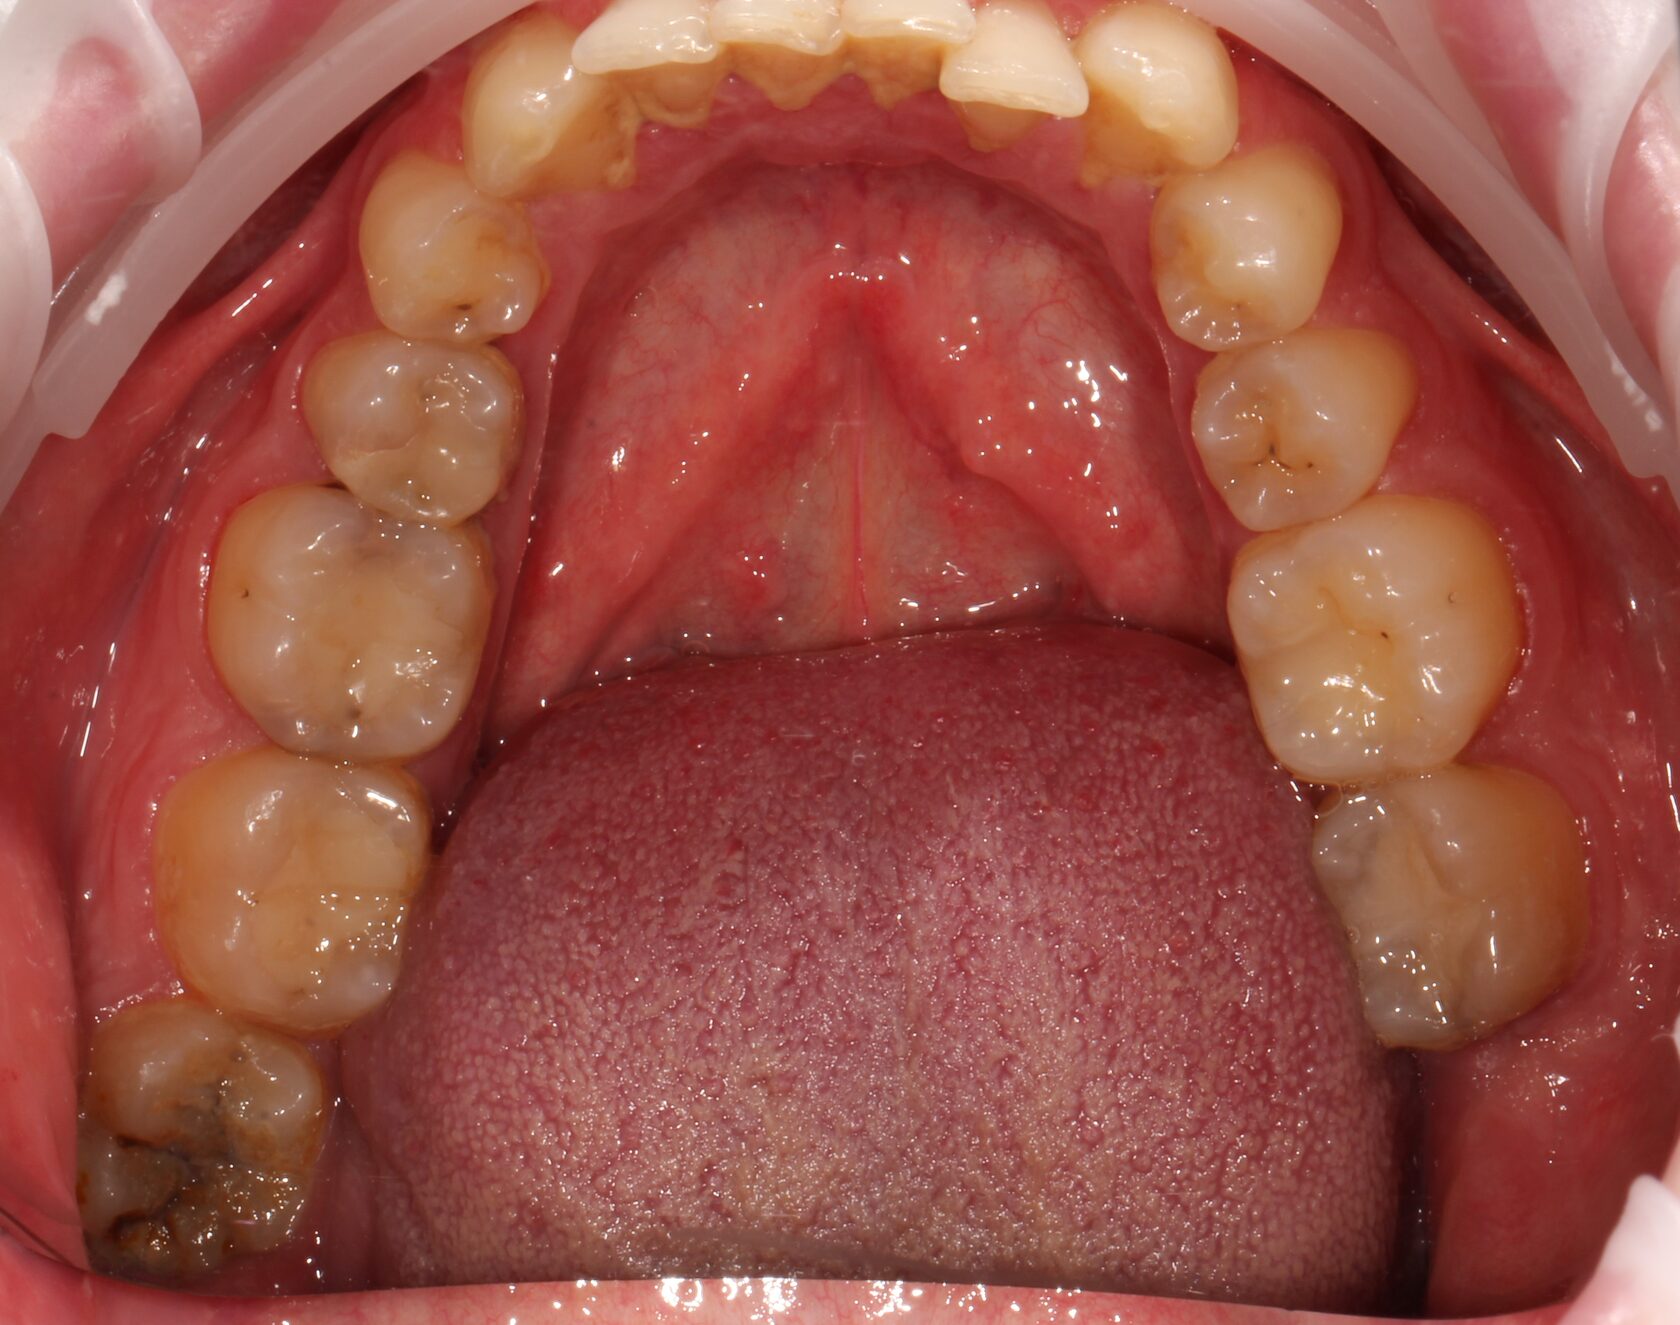

Результат комплексного лечения пациента командой врачей нашей клиники.

Выполнено:

1 Комплексная диагностика и планирование лечения.

2 Лечение всех зубов пораженных кариозным процессом и замена всех несостоятельных пломб.

3 Удаление зубов мудрости.

4 Установка дентальных имплантатов в зоны удаленных зубов.

5 Финальное рациональное протезирование с опорой на дентальные имплантаты.

6 Динамическое наблюдение с 2022 года.